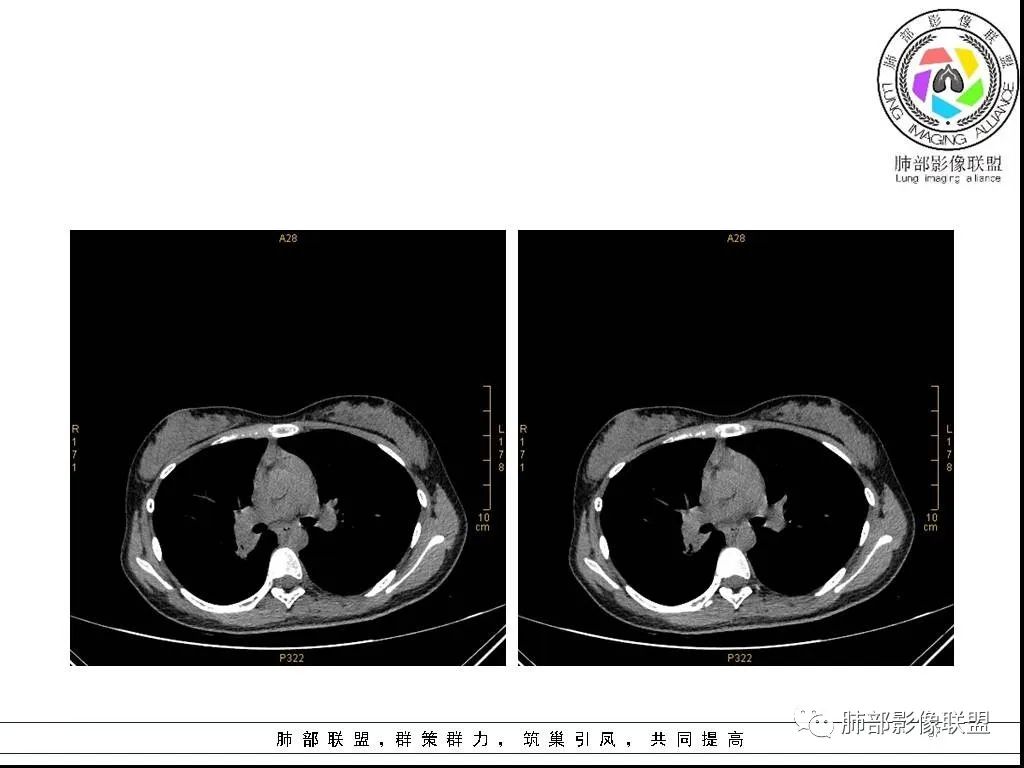

右肺炎症性病变1例CT影像讨论

年轻女性,病程长,咳嗽少痰4个月,辅检未见特殊,CT:右肺团块影,跨叶,主体在下叶背段,外大内小,边缘以膨隆为主,部分平直内收,深分叶,周围有模糊晕,可疑卫星灶,胸膜增厚,糊墙,支气管近端部分进入,粘液栓,有坏死空腔,内壁光整,部分血管侵蚀,强化不均,延迟,明显;同侧R10、7、R4淋巴结肿大,考虑肉芽肿炎,结核,需要与肿瘤鉴别:16岁,女性,诊断肿瘤需要勇气,跨叶多见于炎性,需要进一步活检。

16岁女性,咳嗽,咳痰4月,无发热,白细胞不高,炎性指标(CRP,PPT)不高,血沉增高(75mm/h)。影像表现:右肺胸膜下不规则肿块影,边缘平直,U型凹陷,桃尖征为主,纵隔窗部分层面似有多个结节融合感,近端支气管扩张,堵塞,局部呈鬼脸样改变。边缘可见长短不一毛刺影,周围见晕征,远端见多个小结节卫星灶。胸膜大面积反应性增厚,增强后不均匀中度渐进性强化,局部干酪样坏死可能(CT值-32~-15)内部血管走行较正常,破坏不明显。 医学百科网 | YxBaike.Com

综合分析:病灶边缘平直,U型凹陷,桃尖征为主,周围见晕征,远端见多个小结节卫星灶。胸膜大面积反应性增厚,增强后不均匀中度渐进性强化,加上临床的表现,大方向支持炎性肉芽肿。疾病谱:隐球菌,结核,普通感染,OP,淋巴瘤。结合临床与影像表现:初步诊断:隐球菌可能,诊断依据:一是临床症状及检验指标支持,二是胸膜下肿块,边缘平直,U型凹陷,桃尖征为主,周围见晕征,远端见多个小结节卫星灶,胸膜大面积反应性增厚,增强后不均匀中度渐进性强化,局部干酪样坏死,鬼脸征,血管走行较正常,有破坏,但破坏不明显。需要做隐球菌荚膜抗原检查或穿刺活检进一步明确。鉴别诊断:1、结核,破坏力不明显,坏死不明显,收缩力不够强,无树芽征,临床无结核中毒症状,结核抗体阴性,结核感染T细胞阴性,PPD阴性。但有支气管爬行征,血管有破坏支持结核。2、淋巴瘤:增强后血管破坏不明显支持,其他不支持,所以可能性小,但不完全排除。3、普通细菌感染:白细胞,炎症指标,以及抗炎无效,不支持。4、OP:影像表现要考虑慢性炎症恢复期所致OP,但既然前面分析不支持普通感染,再加上病人咳嗽,咳痰症状持续4月不太支持。